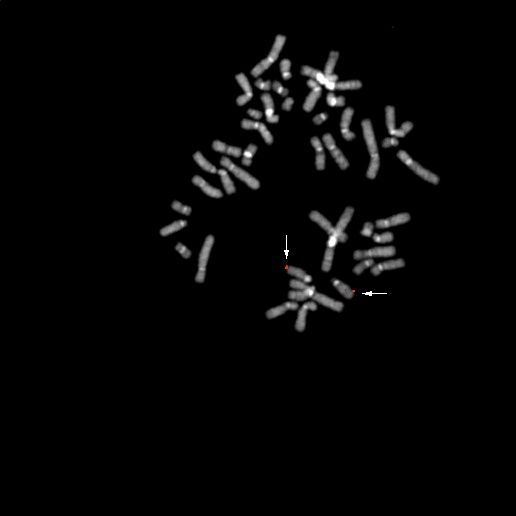

bA185D5